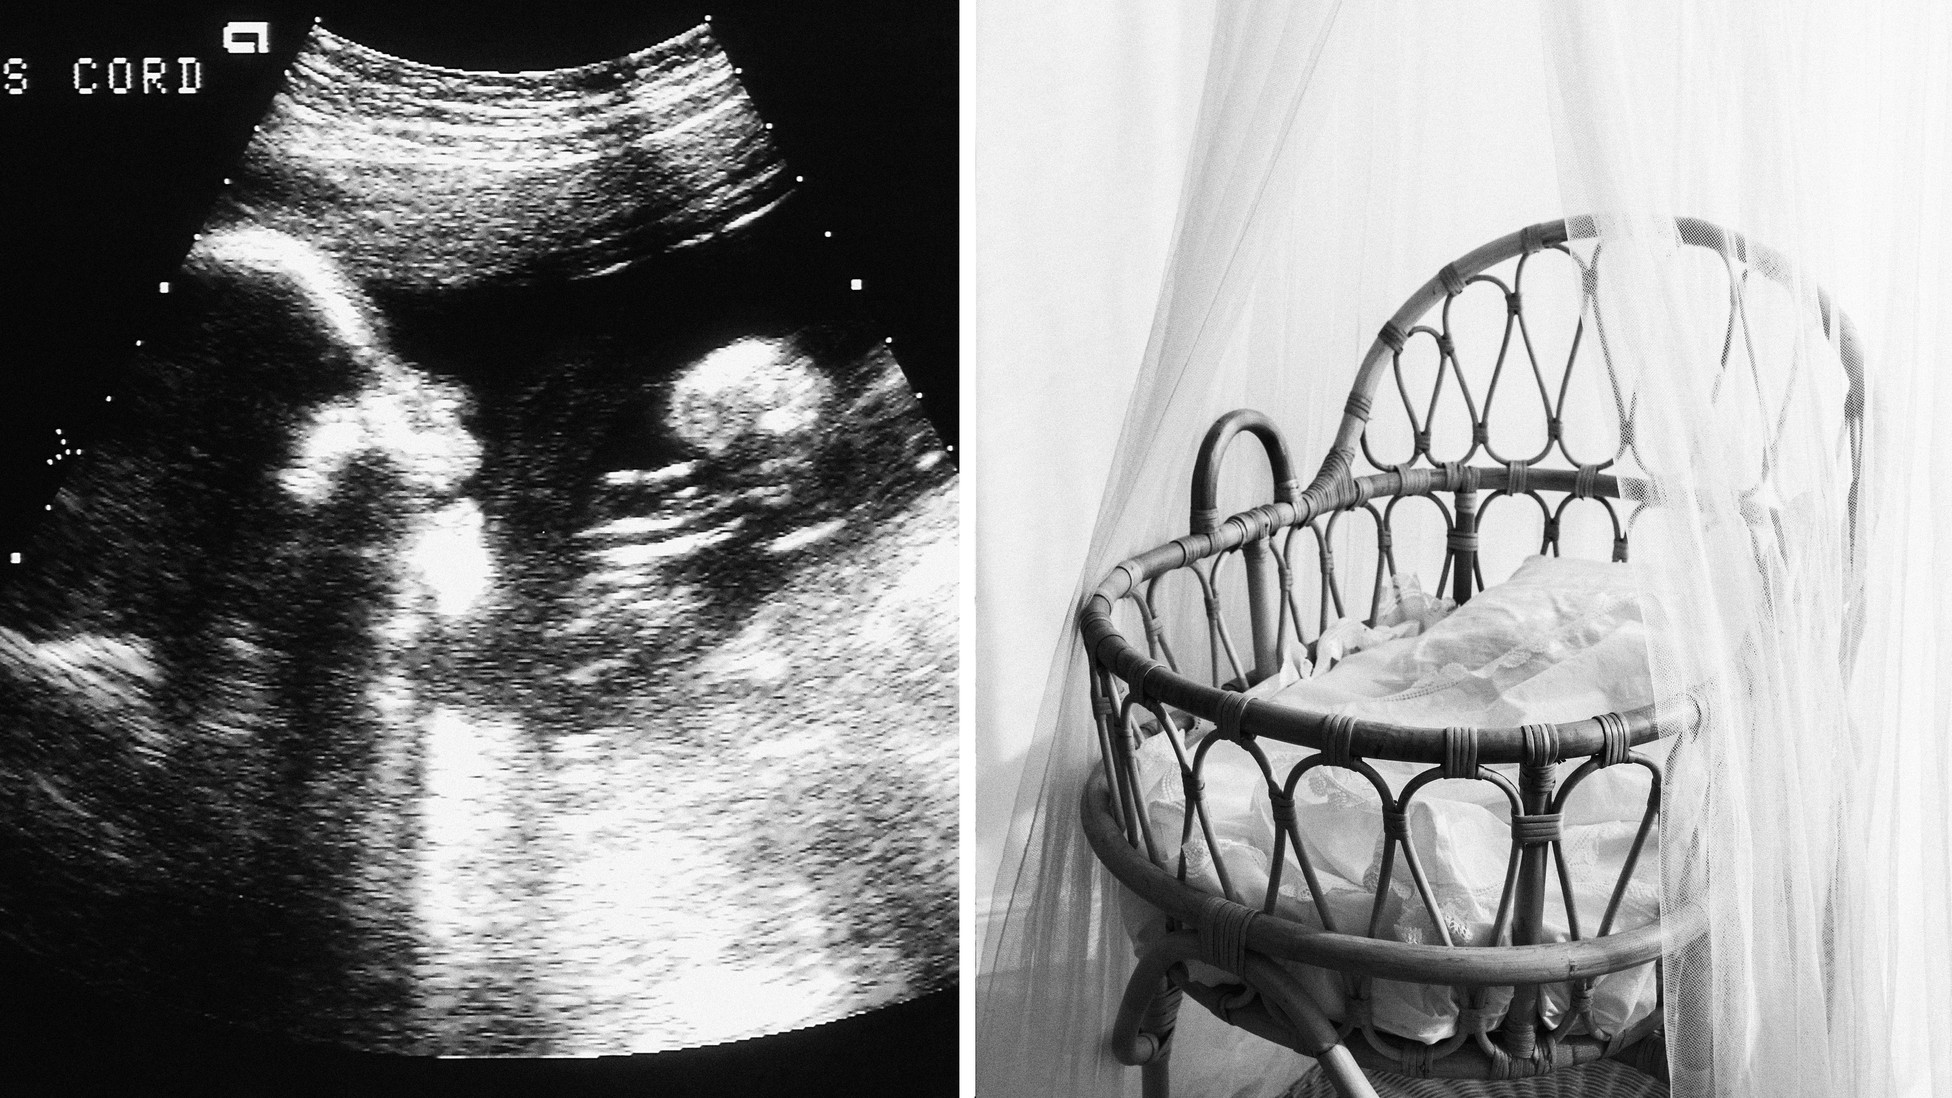

Why I Ghosted My Pregnant Friend After My Miscarriage The Atlantic